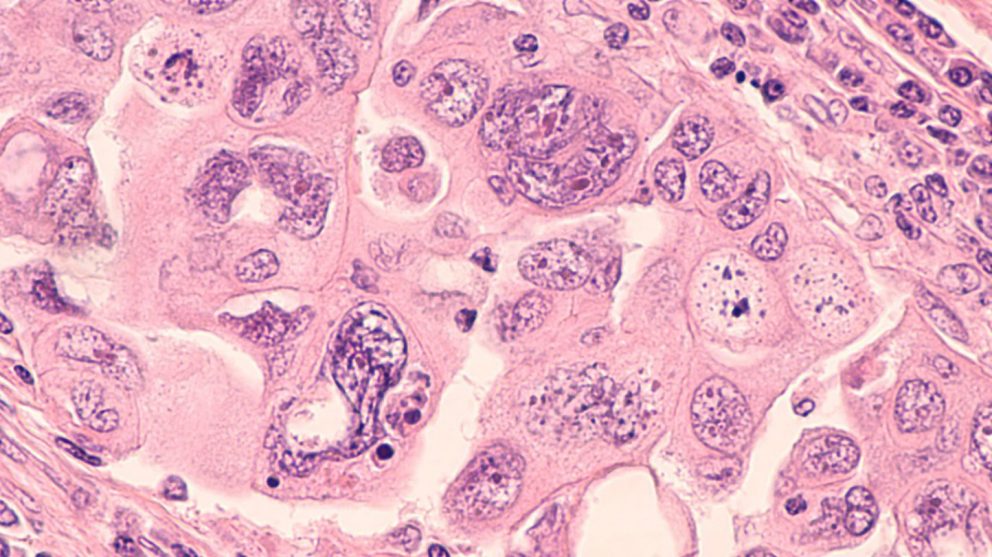

Low-grade serous carcinoma accounts for approximately 5% of all cases of epithelial ovarian cancer and is often diagnosed at a younger age in advanced stages, with a relapse rate of more than 70%. Frontline treatment typically consists of chemotherapy followed by aromatase inhibitor therapy. However, because this rare subtype is relatively resistant to platinum-based chemotherapy, finding an effective targeted therapy remains an unmet clinical need.